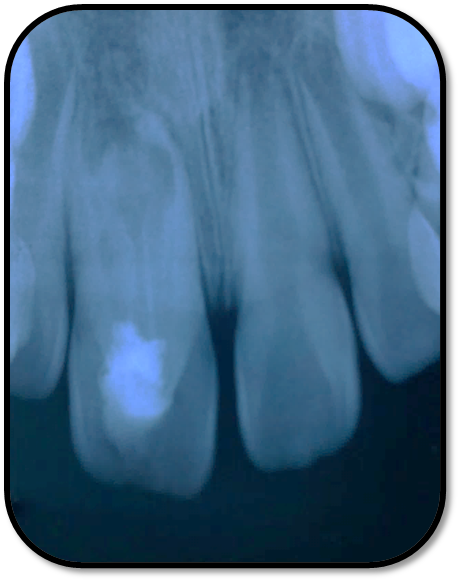

随访复查: 治疗完成后1个月复查:右上1临床检查无阳性体征,叩痛(—),冷测无反应,无松动,牙龈无红肿,充填物完好,牙冠略有变色, X线检查:牙根根继续发育,可见钙化影像形成,如图示 治疗完成后7个月复查:临床检查无阳性体征,充填物完好,牙冠变色局部发黑,叩痛(—),冷测无反应,无松动,牙龈无红肿,临床及 X线检查:牙根继续发育,如图示 治疗完成后17个月复查:临床检查无阳性体征,充填物完好,牙冠变色局部发黑,叩痛(—),冷测无反应,无松动,牙龈无红肿。X线:牙根继续发育,根尖孔已近闭合。如图。 讨论: